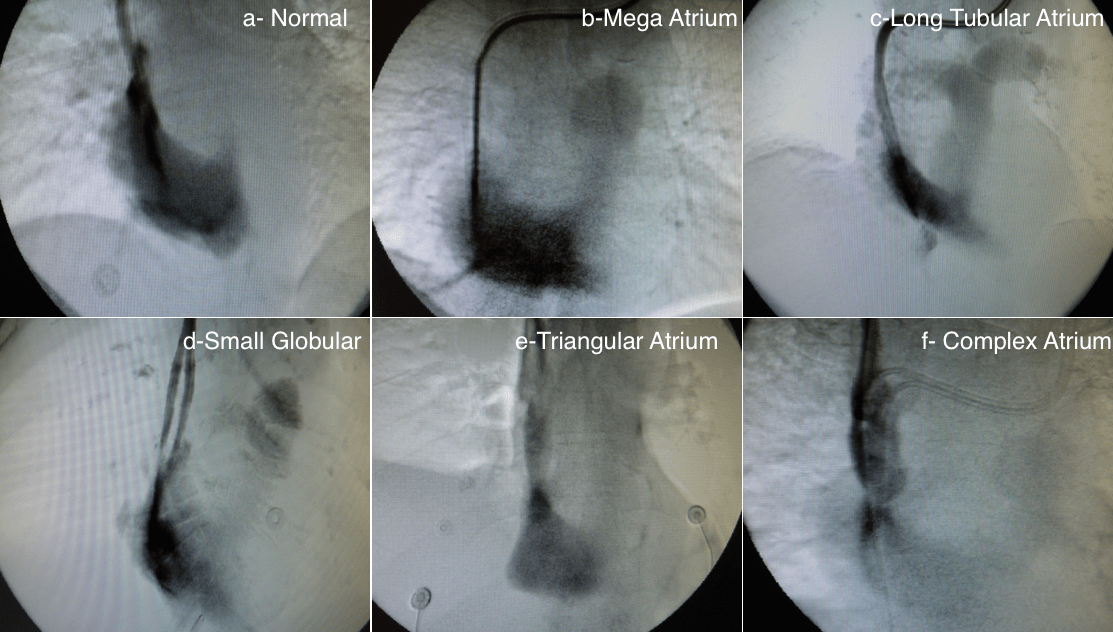

Generally speaking, there are four types of catheter tips: split, step, side-by-side, and two-tip catheters. Each has advantages and disadvantages. There are few studies comparing the effect of the catheter tip on blood flow, catheter survival, and complications with conflicting results. This is probably due to the multiple shapes of the right atrium (Figure 1).

We strongly believe that each patient has their own “perfect catheter” and that one type should not be used for all patients. In our clinical experience, a split catheter is a good choice in normal and deep triangular atria. In a mega atrium, its globular shape will fit any type of catheter. In a long tubular atrium, a step-tip catheter is the best choice, while a side-by-side tip catheter will be more suitable for a small globular atrium. In a complex atrium, consider two-tip catheters. For these reasons, conducting a venogram to determine the shape of the atrium is a good practice.